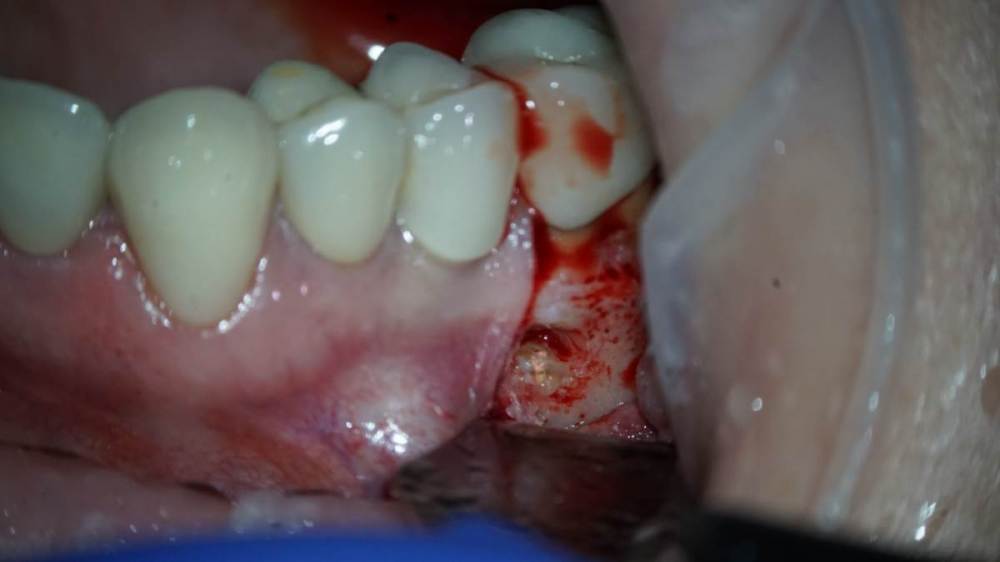

Всем привет!Обострение хронического Pt, ввиду невозможности ортоградной ревизии принято решение об апикальной хирургии.Все манипуляции производятся только под визуальным контролем операционного микроскопа?